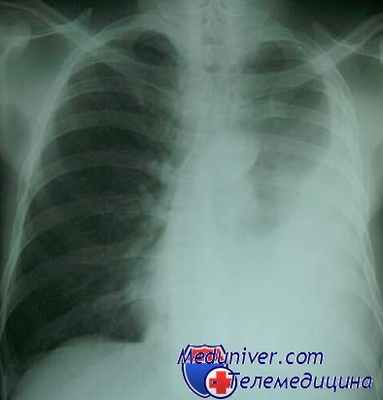

Всем больным после выяснения жалоб, изучения анамнеза, осмотра и лабораторного обследования выполняли стандартную рентгенографию грудной клетки в 2 проекциях. Во всех наблюдениях рентгеновское исследование позволило получить информацию, которой было вполне достаточно для правильной диагностики заболевания (табл. 2).